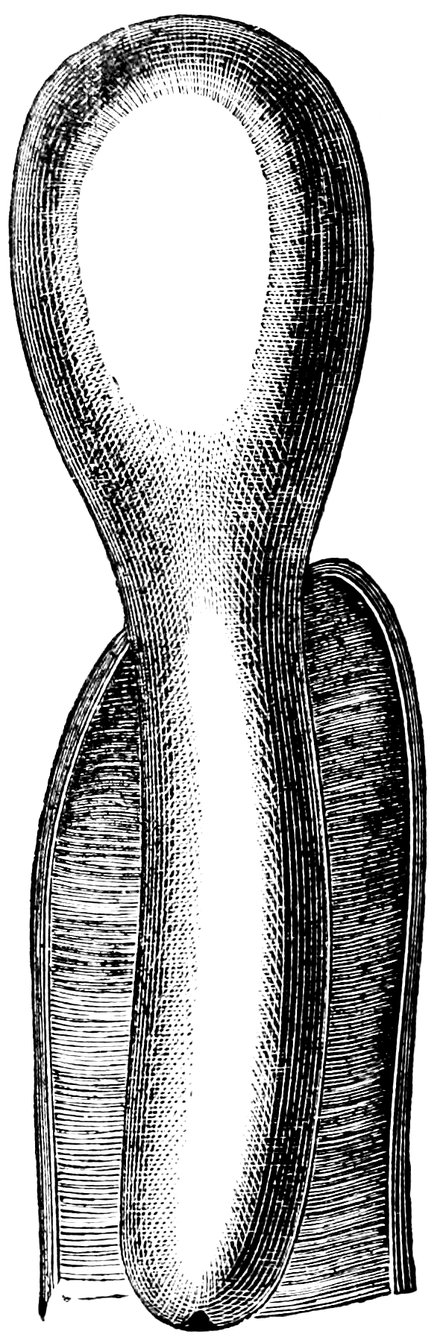

| 65. | Septate Hymen, the septum having a tendinous consistency | 324 |